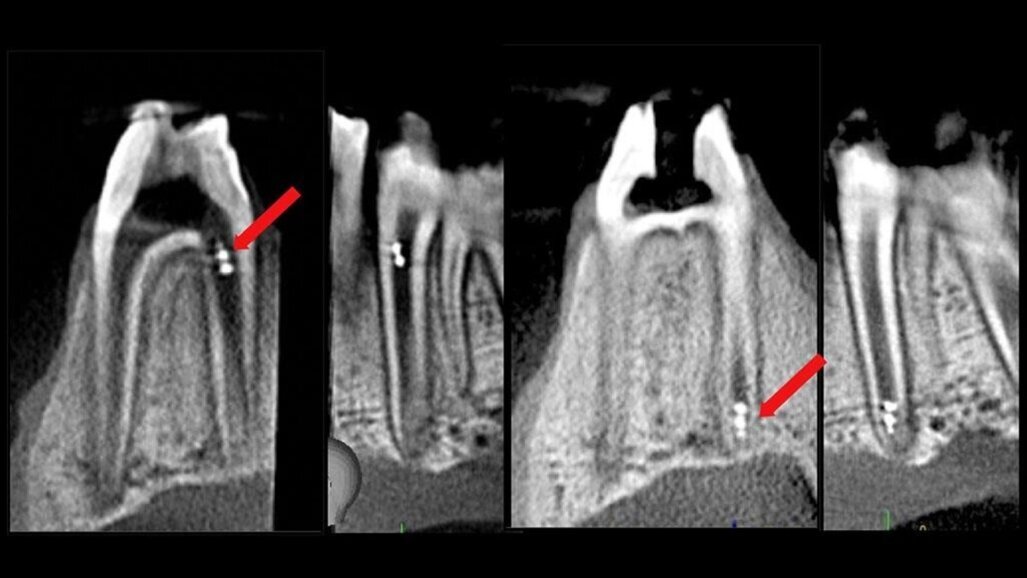

“Onze bevindingen tonen de haalbaarheid van de veelzijdigheid van microrobotica om moeilijk bereikbare wortelkanaaloppervlakken te bereiken voor het kapotmaken, verwijderen en ophalen van biofilm voor microbiële detectie in real-time. Verder bewijzen we de haalbaarheid van het volgen van de robot in het wortelkanaal met behulp van de huidige klinische imaging technieken,” vervolgt hij.